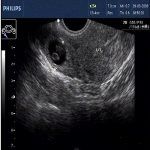

在医疗技术发达的今天,对于异位妊娠宫外孕,诊断性刮宫,后穹隆穿刺是已经废除的技术,大多情况下,异位妊娠患者经病史、妇科检查、血β–HCG测定、B超检查后即可对早期异位妊娠作出诊断,但对部分诊断比较困难的病例,直接在3D腹腔镜直视下进行检查,可及时明确诊断,并可同时手术治疗。